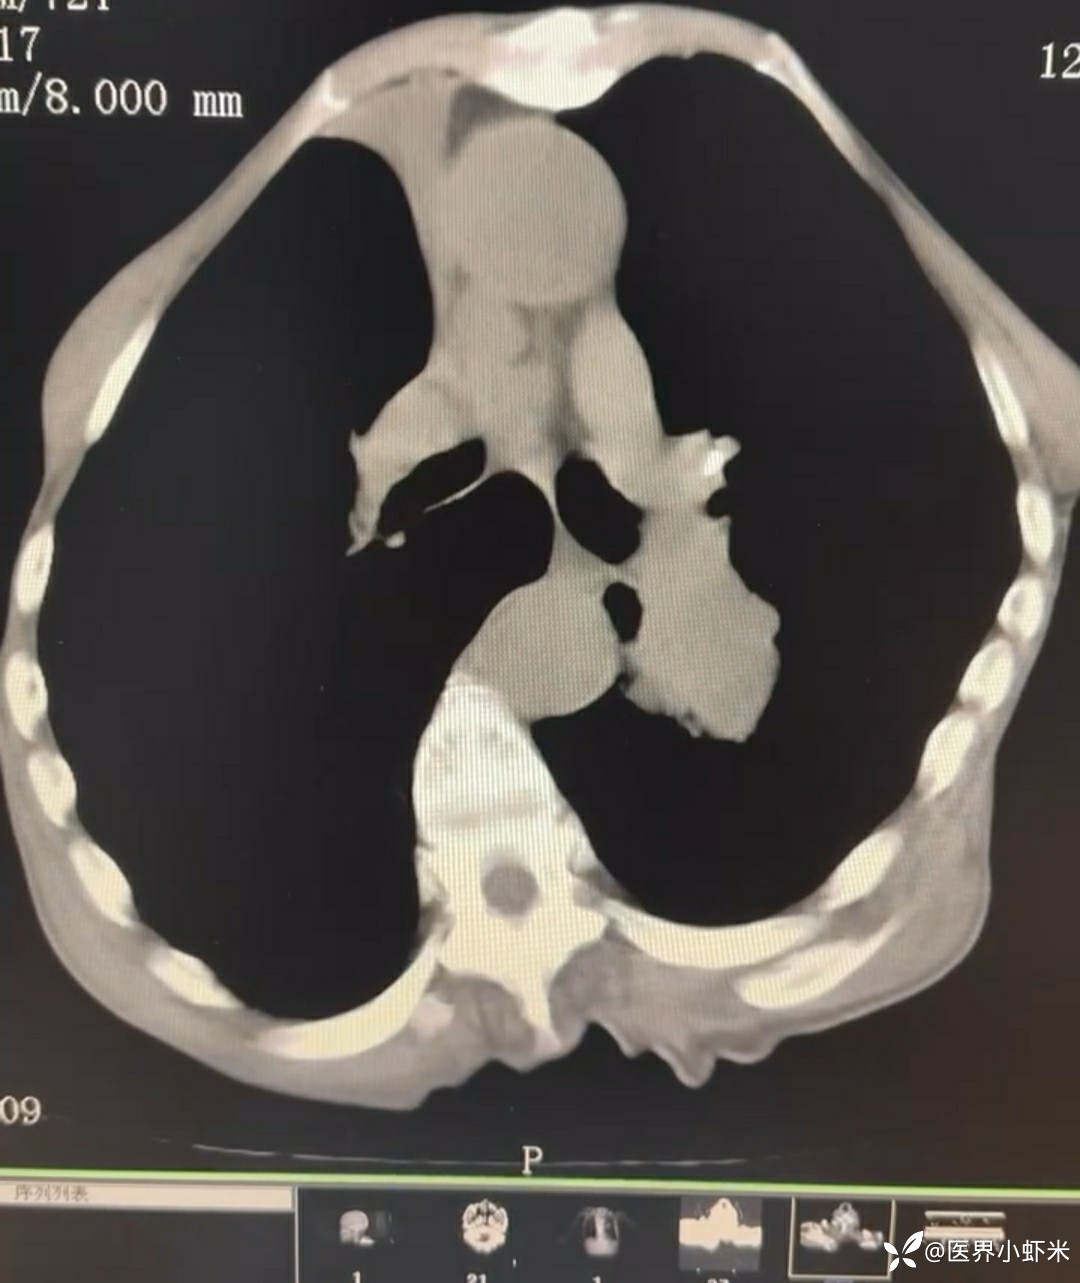

目前考虑:1.中央型肺癌伴2.肝继发恶性肿瘤?2.左丘脑继发恶性肿瘤?3.左丘脑出血?4.肾功能不全5.肝功能异常6右肾萎缩7.肺部感染8.慢性阻塞性肺病7.高血压3级(极高危)。